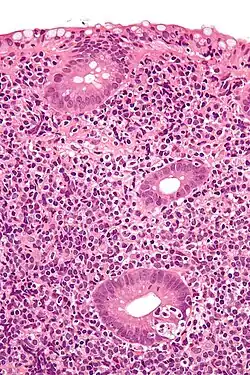

In pathology, lymphoepithelial lesion refers to a discrete abnormality that consists of lymphoid cells and epithelium, which may or may not be benign.

It may refer to a benign lymphoepithelial lesion of the parotid gland or benign lymphoepithelial lesion of the lacrimal gland, or may refer to the infiltration of malignant lymphoid cells into epithelium, in the context of primary gastrointestinal lymphoma.[1]

In the context of GI tract lymphoma, it is most often associated with MALT lymphomas.[1]